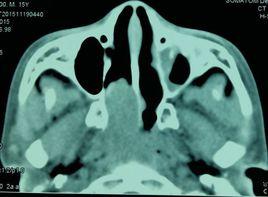

中鼻甲切除術適用於:

1.中鼻甲肥大與鼻中隔接觸引起反射性頭痛或中鼻甲後端肥大而刺激蝶齶神經者。

2.中鼻甲肥大阻塞嗅溝影響嗅覺及總鼻道通氣者。

3.為保證鼻內手術順利進行,如篩竇開放術、鼻額管擴大術、蝶竇自然口擴大術等。

4.中鼻甲肥大,影響上頜竇、額竇及前組篩竇引流者。

5.中鼻甲後端肥大形成息肉樣變,突向鼻後孔者。